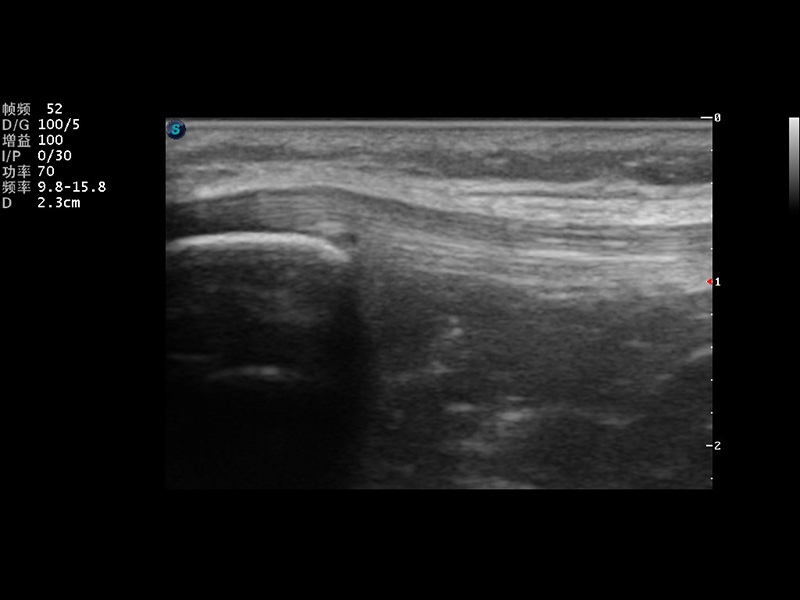

S9便携式彩色多普勒超声诊断仪是九州酷游研发的高端便携彩超设备,外观设计新颖、产品性能卓越。S9在便携超声领域采用了突破传统的触摸屏交互设计,并以先进的软件硬件技术和设计理念,为您带来清晰的图像质量、稳定的工作性能和便捷的操作体验。

μ-Scan微米成像